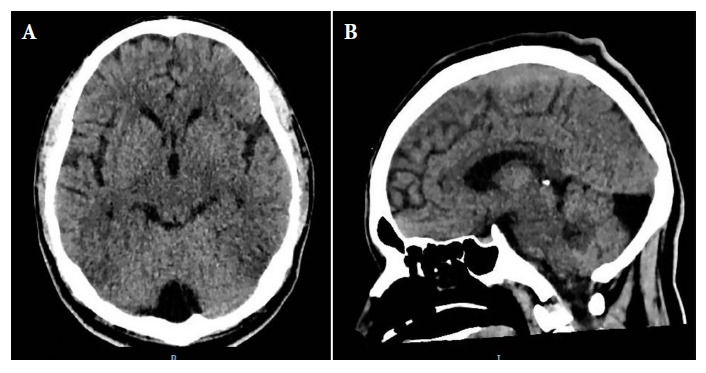

We report a case of Cryptococcus gattii meningitis in a patient with HIV in the Peruvian Amazon. A 36-year-old male patient with severe neurological symptoms that was diagnosed by cerebrospinal fluid culture. Although liposomal amphotericin B and flucytosine are considered the standard antifungal therapy, due to a lack of resources, an alternative treatment of amphotericin B deoxycholate and fluconazole was used. Even with this alternative, treatment faced challenges due to the persistence of the microorganism. This case highlights the importance of considering C. gattii in the differential diagnosis of cryptococcal meningitis in immunocompromised patients, even in areas where the prevalence of this pathogen is low. The effectiveness of treatment and the patient's survival underscore the need for diagnostic and therapeutic strategies adapted to resource-limited settings.